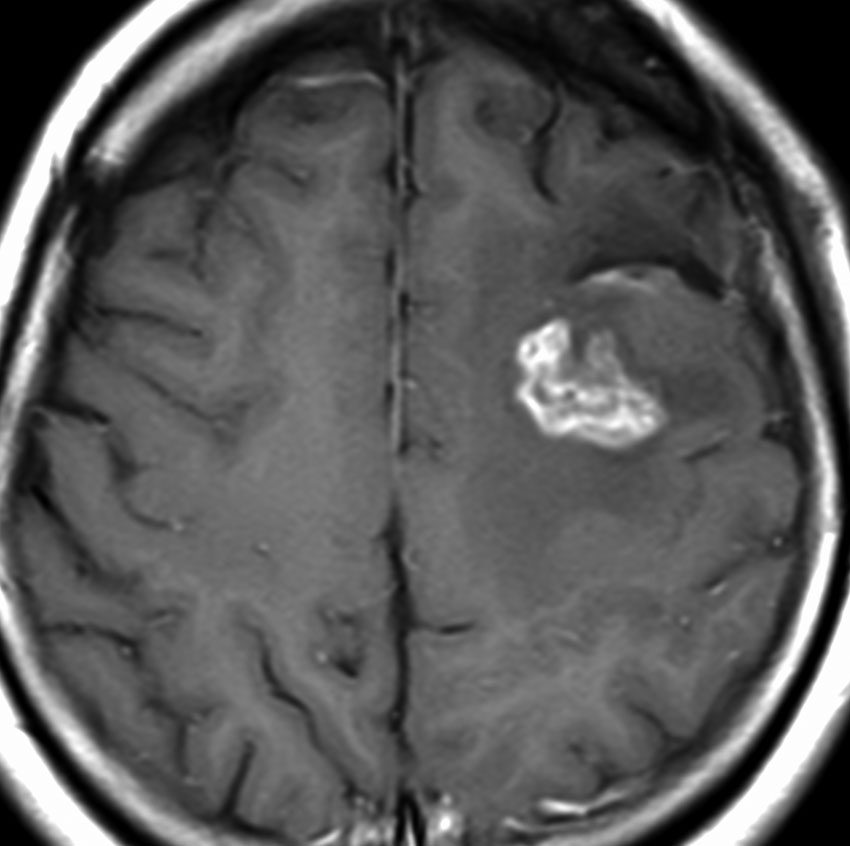

T2-FLAIR mismatch sign (T2とフレアの信号が違うこと)

protoplasmic astrocytomaに特徴的なMRI所見です。T2強調画像(左側)では白く(強い均一な高信号)見えます。でもフレア画像(右側)では白く縁取ったように見えます。びまん性星細胞腫の大きな特徴とされます。内部がとても柔らかいドロドロした腫瘍のこともあります。